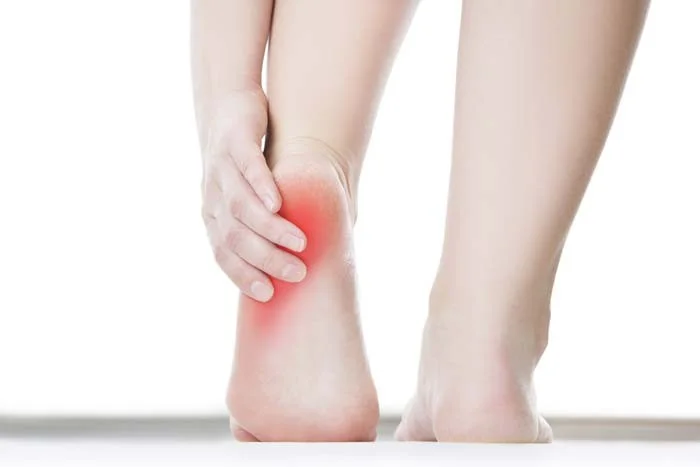

Symptoms - Plantar Fasciitis

- Gradual onset

- “Start-up Pain”:

- When wake up in the morning

- After sitting for some time

- Pain:

- Pins and needles, or sharp, or persistent aches

- At hind & mid foot area

- Improves with:

- Walking for sometime

- Elevation

- NSAID